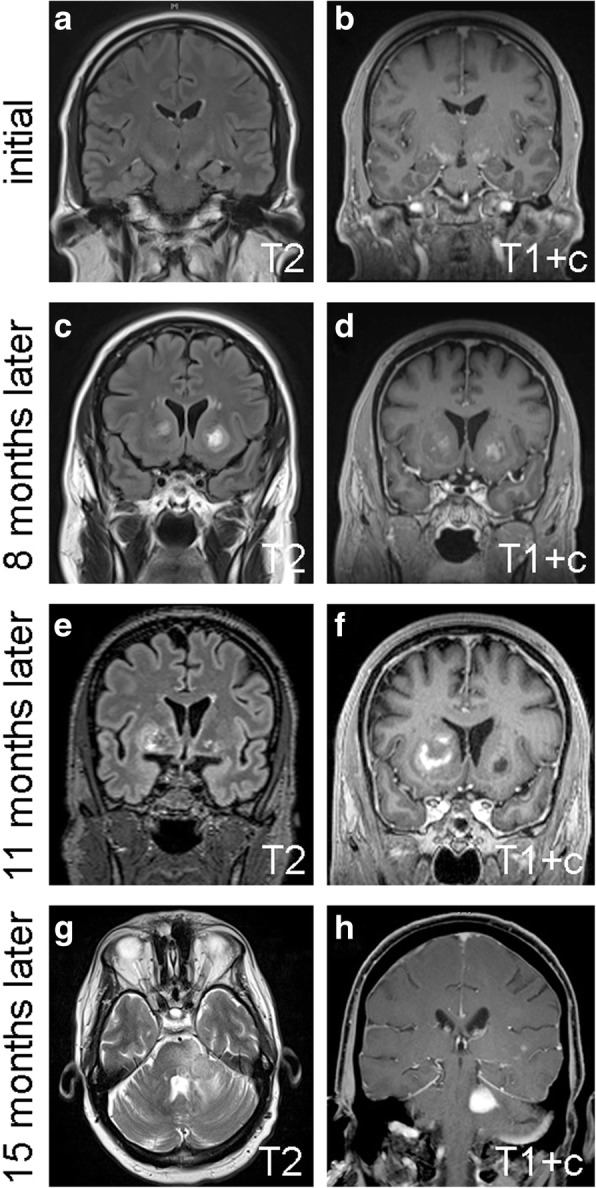

Fig. 1.

Serial MRIs. The initial set of MRIs showed T2 hyperintensity and some contrast enhancement in the bilateral internal capsules (a, b). Eight months later, a second set of MRIs showed new enhancing lesions in the bilateral basal ganglia (c, d). Eleven months after initial presentation, the right basal ganglia lesion appeared to grow, whereas the lesion in the left basal ganglia diminished (e, f). In the final set of MRI, 15 months after initial presentation, the right basal ganglia lesion was unchanged (not shown), and a new enhancing mass appeared in the left middle cerebellar peduncle (h). c = contrast

The patient was a 60 year-old previously healthy man who presented to an outside institution with a rapid onset of dysarthria without aphasia, as well as blurred vision in his right eye without ptosis. The patient had a history of high blood pressure (controlled with losartan) and acid reflux, but no recurring infections, headaches, abnormal clotting or bleeding, night sweats, dysphagia, or weakness. At the outside institution, a full battery of laboratory testing, including complete blood count, complete metabolic profile (CMP), erythrocyte sedimentation rate, vasculitis panel, autoimmune panel, and myasthenia gravis panel, was negative. A stroke was therefore initially suspected, but magnetic resonance imaging (MRI) showed T2 hyperintensity tracking along both corticospinal tracts from the corona radiata through the posterior limb of both internal capsules and cerebral peduncles, as well as some matching contrast enhancement (Fig. 1a-b). Although nonspecific, this was originally felt to be most consistent with a neurodegenerative disease such as amyotrophic lateral sclerosis (ALS) or other metabolic disorder. At a second external institution, electromyography was obtained that ruled out ALS.

The patient remained fairly stable for the next several months, and declined follow-up appointments and imaging. Four months after initial presentation, he developed bilateral blurry vision and leg weakness, yet still declined follow-up care until arriving at our institution 8 months after his initial presentation. An MRI at that time showed new enhancing lesions in the bilateral basal ganglia (Fig. 1c-d), raising concern for CNS vasculitis. Yet aside from a mild elevation of antinuclear antibodies, his serum protein electrophoresis, vitamin B12, vitamin D, folate, and repeat autoimmune and CMP panels were all within normal limits. Computerized tomography of the patient’s chest, abdomen, and pelvis were all negative for lymphadenopathy. Flow cytometry on a cerebrospinal fluid sample was negative for atypical lymphocytes; only 1% of the lymphocytes present in the cerebrospinal fluid were CD19+ B cells.

Up to this point, the comprehensive workup had been inconclusive, so no treatment had yet been administered, including steroids. But when another MRI showed further progression of the right basal ganglia lesion 3 months later (11 months after initial presentation, Fig. 1e-f), a stereotactic biopsy of the right basal ganglia was taken in an effort to establish a diagnosis. The tissue showed brisk perivascular and parenchymal lymphocytic infiltration (Fig. 2), but no evidence of vessel wall damage. All the lymphocytes appeared small and mature, with no mitoses anywhere in the biopsy. While immunohistochemical studies showed a strikingly high number of CD20-positive B cells, relative to what is typically seen in inflammatory diseases of the brain, as well as large numbers of admixed CD3/5-positive T cells, the Ki67 proliferation index was only 5% (Fig. 3). Other stains, including CD10 and EBV-encoded RNA (EBER) in-situ hybridization were negative (Fig. 3), as was Bcl1 (not shown). Luxol fast blue showed no lipid-laden macrophages or other evidence of demyelination (not shown). Flow cytometry performed on an unfixed portion of the biopsy was negative for abnormal clonal subpopulations, and molecular analysis was negative for immunoglobulin heavy chain gene rearrangement. The biopsy was then sent for external review by additional neuropathology and hematopathology experts, who concurred that a neoplastic process could not be proven.

Four months after the first biopsy (15 months post initial presentation), the patient developed unsteady walk, cheek and tongue numbness, post-meal emesis, slurred speech, and worsening bilateral leg weakness. A fourth MRI showed a new enhancing region in the left middle cerebellar peduncle (Fig. 1g-h), prompting a biopsy of the peduncular lesion. This time, the tissue showed an obvious malignancy, composed of cells with large, highly atypical nuclei and clumped chromatin, scant cytoplasm, and abundant mitoses (Fig. 2). Unlike the prior biopsy, the repeat biopsy showed a clear preponderance of CD20-positive B cells, as well as an extremely high Ki67 proliferation index approaching 100% (Fig. 3). MUM1 and cMYC were positive in 80 and 40% of the tumor cells, respectively, while Bcl2 was present in 80% of cells and Bcl6 was expressed by only 10–15% of the cells overall (Fig. 4). CD5, CD10, and EBER were all negative in the neoplasm (Fig. 3). Immunoglobulin heavy chain gene PCR showed clonal rearrangement, whereas a fluorescent in situ hybridization test for MYC rearrangement was negative (not shown). No flow cytometry was done on the second biopsy. Subsequent computerized tomography showed no evidence of systemic lymphadenopathy.